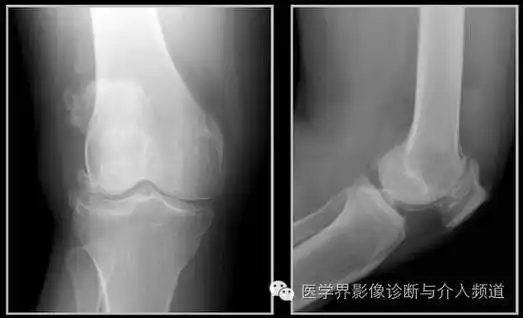

上下楼梯疼痛警惕髌骨软化症如何诊治

骨,关节基本病变x线表现 骨质软化 o型腿 x型腿

(2)下肢畸形:由于骨质软化关节松弛在重力作用下出现o形腿,x形腿.